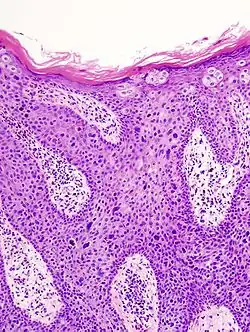

In situ disease

Bowen's disease is essentially equivalent to and used interchangeably with cSCC in situ, when not having invaded through the basement membrane.[12] Depending on source, it is classified as precancerous[13] or cSCC in situ (technically cancerous but non-invasive).[48][49] In cSCC in situ (Bowen's disease), atypical squamous cells proliferate through the whole thickness of the epidermis.[12] The entire tumor is confined to the epidermis and does not invade into the dermis.[12] The cells are often highly atypical under the microscope, and may look more unusual than the cells of some invasive squamous-cell carcinomas.[12]

-

cSCC in situ, high magnification, demonstrating an intact basement membrane.[12] -